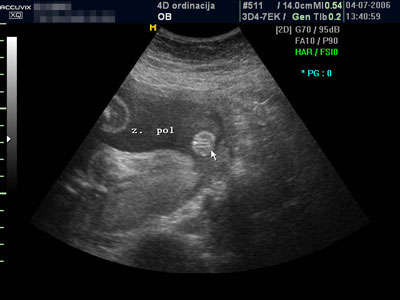

• www.4dordinacija.com ŠTA JE 4D ULTRAZVUK? Ultrazvuk koji nudi četvorodimenzionalan prikaz ploda. Šta to zapravo znači? Direktan uvid u dešavanja u majčinom stomaku tj. „live“ (uživo) prikaz izgleda i ponašanja ploda. Dakle, 4D je najsavremeniji prozor u bebin svet. ZAŠTO 4D? Zato što nudi mnogo više od samo „lepe slike“. Višestruko povećava mogućnost potvrđivanja normalnosti razvoja ploda u rizičnoj trudnoći, kao i rano otkrivanje neočekivanih abnormalnosti ploda. Lice, šake i stopala, česte su mete pojave izolovanih neočekivanih abnormalnosti (koje mogu i ne moraju biti genski uslovljene). Njihov fascinantan prikaz pri 4D pregledu ne dozvoljava propust, što ovaj pregled čini superiornim u odnosu na dosadašnje tradicionalne preglede. Dakle, 4D ultrazvuk obezbeđuje novu dimenziju infor...